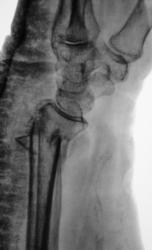

Катенёв Валенти... Дата публикации 23.04.2009, 18:55 Травма. Пациентка направлена на рентгенографию правого лучезапястного сустава. Проведена рентгенография, насколько это возможно, в стандартных проекциях. После репозиции отломков и наложения гипсовой повязки произведено рентген-контроль. Чт, 23/04/2009 - 19:21 #1 Dr.Mario Не на сайте Был на сайте: 11 лет 6 месяцев назад Зарегистрирован: 06.08.2008 - 08:44 Публикации: 920 плохо, очень плохо. Let me see... radiographia.ru Чт, 23/04/2009 - 20:48 #2 Vega Не на сайте Был на сайте: 4 месяцев 3 недели назад Зарегистрирован: 22.01.2009 - 19:16 Публикации: 1087 Да, нужно оперировать